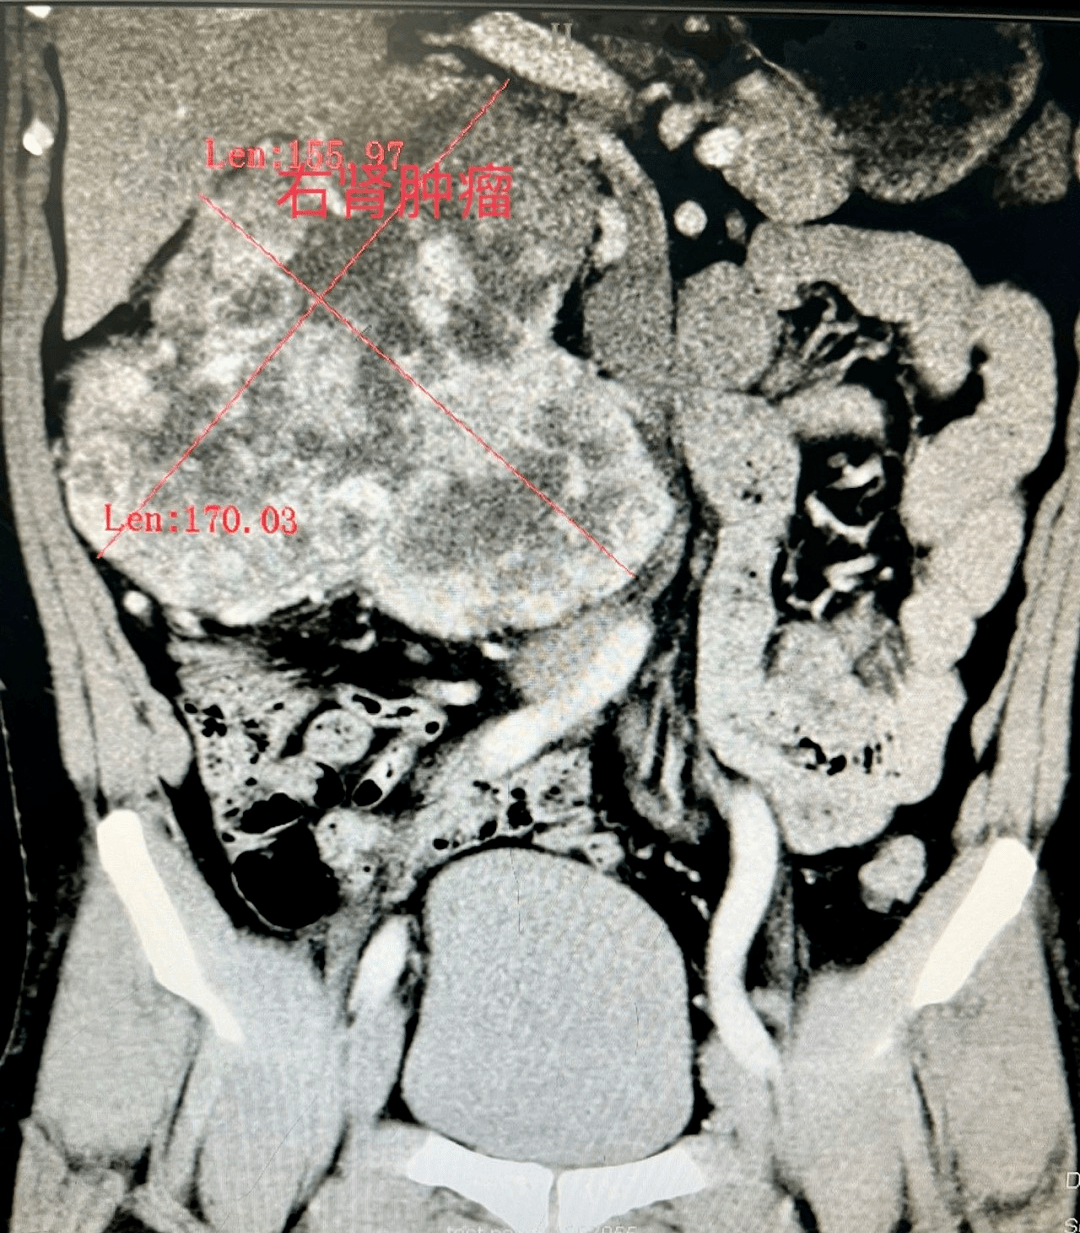

右肾肿瘤

右肾上腺巨大肿瘤